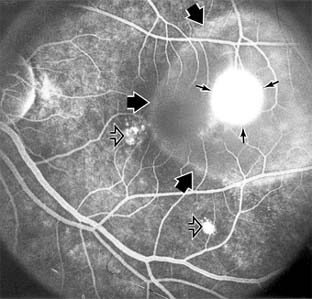

MACULAR EDEMA

Retinal edema involving the macula may be associated with a variety of intraocular inflammatory diseases, retinal vascular diseases, intraocular surgery, inherited or acquired retinal degenerations, medications, macular membranes, or unknown causes. Macular edema may be diffuse, with nonlocalized intraretinal fluid causing thickening of the macula. When edema fluid accumulates in honeycomb-like spaces of the outer plexiform and inner nuclear layers, it is called cystoid macular edema. On fluorescein angiography, fluorescein dye leaks from the perifoveal retinal capillaries and accumulates in a flower-petal pattern about the fovea (Figure 10-4).

Figure 10-4

Figure 10-4: Flower-petal pattern of fluorescein dye in a patient with cystoid macular edema after cataract surgery.